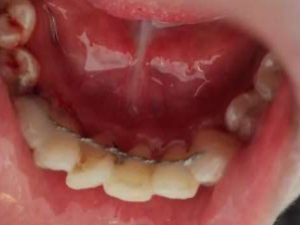

placed for four weeks with weekly evaluation. At end of four weeks, splint was removed (Figure 1 b) with diamond bur. After one year of continuous three months follow up, the patient referred in the Endodontics for further treatment. At two years of follow up, color, contour, position of gingiva was excellent, well maintained alveolar bone height (Figure 2) & the patient was completely satisfied with result obtained.

Figure 2